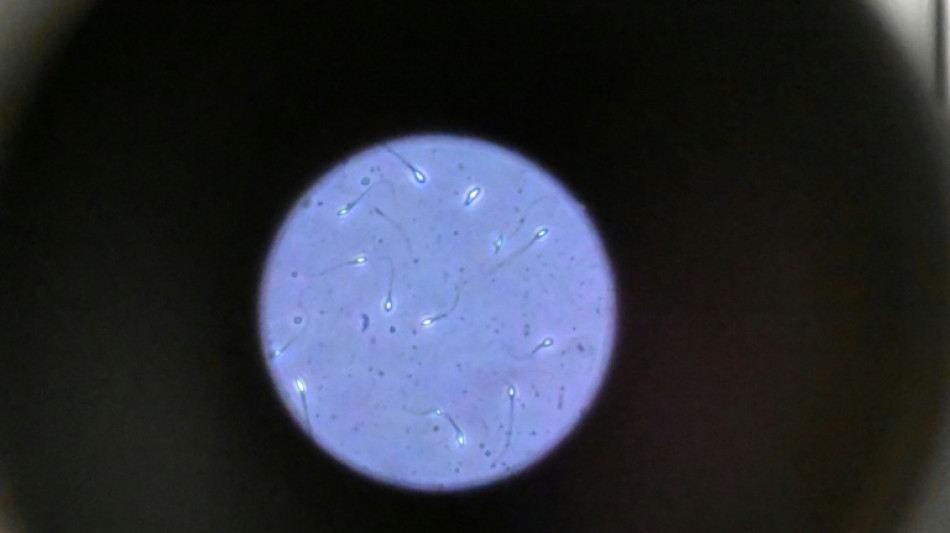

Dans l'espace, les spermatozoïdes ont du mal à trouver leur chemin

Dans l'espace, les spermatozoïdes ont du mal à trouver leur chemin vers l'ovule en raison de la microgravité, qui perturbe aussi le développement des embryons, selon une étude publiée jeudi dans Communications Biology.

Une des difficultés réside dans le fait que le sperme n'est plus attiré vers le bas par la gravité terrestre.

"Les spermatozoïdes doivent activement trouver leur chemin vers l'ovule et cette étude est la première à tester leur capacité à le faire dans des conditions semblables à ce qui se passe dans l'espace", explique à l'AFP Nicole McPherson, autrice principale de l'étude et chercheuse à l'Université d'Adelaïde (Australie).

Son équipe a utilisé une chambre en plastique imitant l'appareil génital féminin, qui leur a servi de "parcours d'obstacles miniature". "Voyez ça comme un minuscule circuit de course... Les spermatozoïdes étaient introduits à une extrémité et devaient nager jusqu'à l'autre bout", décrit-elle.

Les chercheurs ont testé successivement du sperme de souris et humain dans ce dispositif placé dans un appareil en constante rotation pour simuler la microgravité.

Les gamètes ont été environ 50 % moins performants pour naviguer à travers ce parcours que sous la gravité terrestre. Cela équivaut à une baisse de 30% du taux de fécondation réussie, selon les résultats de l'étude.